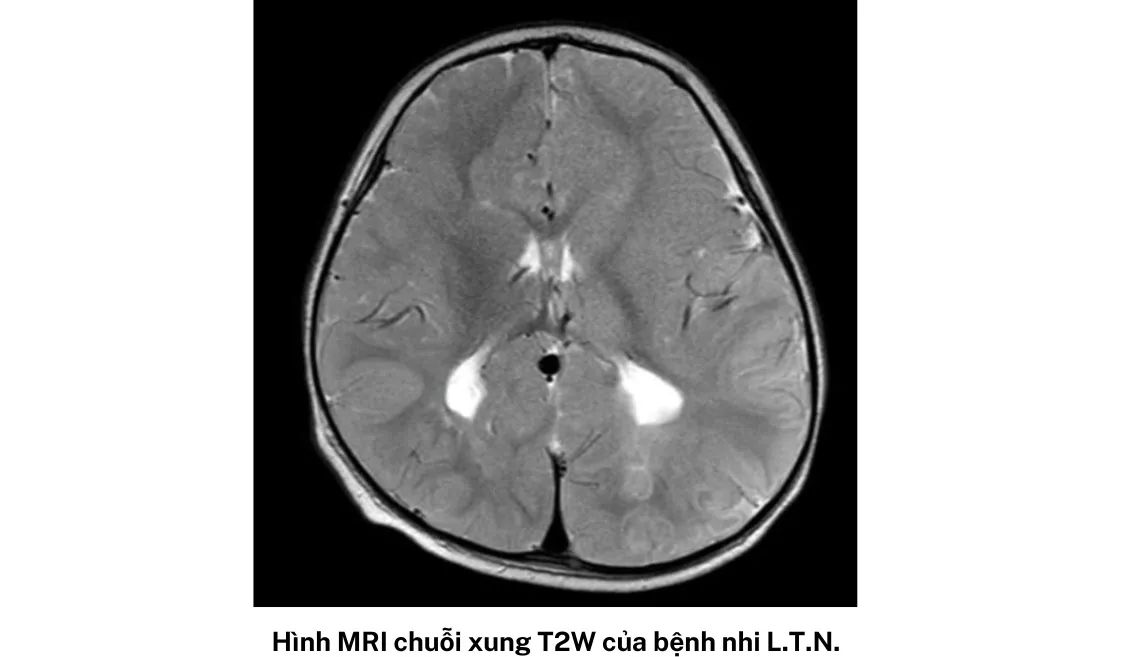

Trường hợp thứ hai là bệnh nhi nữ, sinh năm 2020, tại TPHCM nhập khoa vào ngày cuối tháng 5.

Bé có tiền sử động kinh toàn thể từ 14 tháng tuổi và đang điều trị Depakin. Qua 10 ngày tích cực điều trị, tri giác bé có cải thiện chậm, có nhịp tự thở tốt và cai được máy thở, tiếp tục kiểm soát động kinh và vật lý trị liệu vận động.

Hội chứng hai bé gặp phải còn gọi là hội chứng HHE, là một bệnh hiếm gặp được phát hiện lần đầu vào năm 1960. Bệnh có trạng thái co giật nửa người kéo dài trên trẻ sốt dưới 4 tuổi, gây liệt nửa người cùng bên co giật và teo não bán cầu đối bên.

Bác sĩ Việt nhấn mạnh, ở giai đoạn cấp tính, bệnh nhân xuất hiện nhiều cơn co giật khó kiểm soát, tổn thương và phù não một bên bán cầu não. Nếu không kiểm soát tốt, bệnh nhân có thể liệt nửa người suốt đời, di chứng não và sống đời sống thực vật, thậm chí có thể tụt não dẫn đến tử vong.